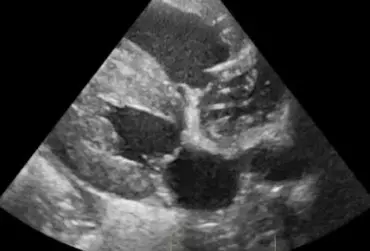

Echo serca z widoczną obecnością dużej liczby nicieni w prawym przedsionku serca (4)

16 kwietnia 2019

Wojciech Atamaniuk

Echo serca z widoczną obecnością dużej liczby nicieni w prawym przedsionku serca (3)

Echo serca z widoczną obecnością dużej liczby nicieni w prawym przedsionku serca (2)

Echo serca z widoczną obecnością dużej liczby nicieni w prawym przedsionku serca (1)